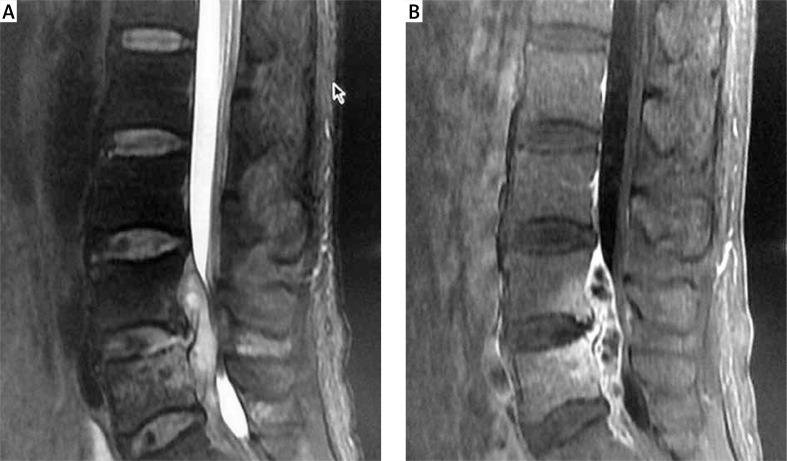

We enrolled 12 patients who underwent intervertebral disc infections with epidural abscess. The clinical efficacy was evaluated by visual analog scale (VAS) and standard Macnab's evaluation. Postoperative computed tomography and magnetic resonance imaging were also used to evaluate the clinical efficacy.

我们纳入了12例患有椎间盘感染合并硬膜外脓肿的患者。通过视觉模拟量表(VAS)和标准的Macnab评估来评估临床疗效。术后还使用计算机断层扫描和磁共振成像来评估临床疗效。